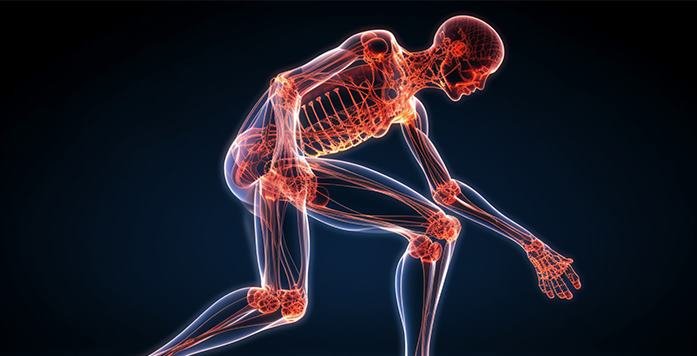

Ankylosing spondylitis is mostly affecting the spine, resulting in inflammation of the sacroiliac joints (the joints that connect the pelvis to the spine) and vertebrae (the bones that make up the spine). Psoriatic, reactive, and enteropathic arthritis are among the rheumatic illnesses that comprise the spondylarthritis category, which includes AS. Ankylosing spondylitis is characterized by inflammation of the sacroiliac joints, which can cause lower back and buttock discomfort and stiffness.